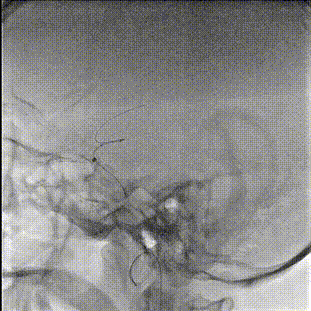

术中缓慢释放NeuroStellar®颅内支架头端后系统稳定,随后释放至支架尾端,造影提示支架打开满意,贴壁满意。

最后经6F中间导管正侧位造影留存影像后结束手术。